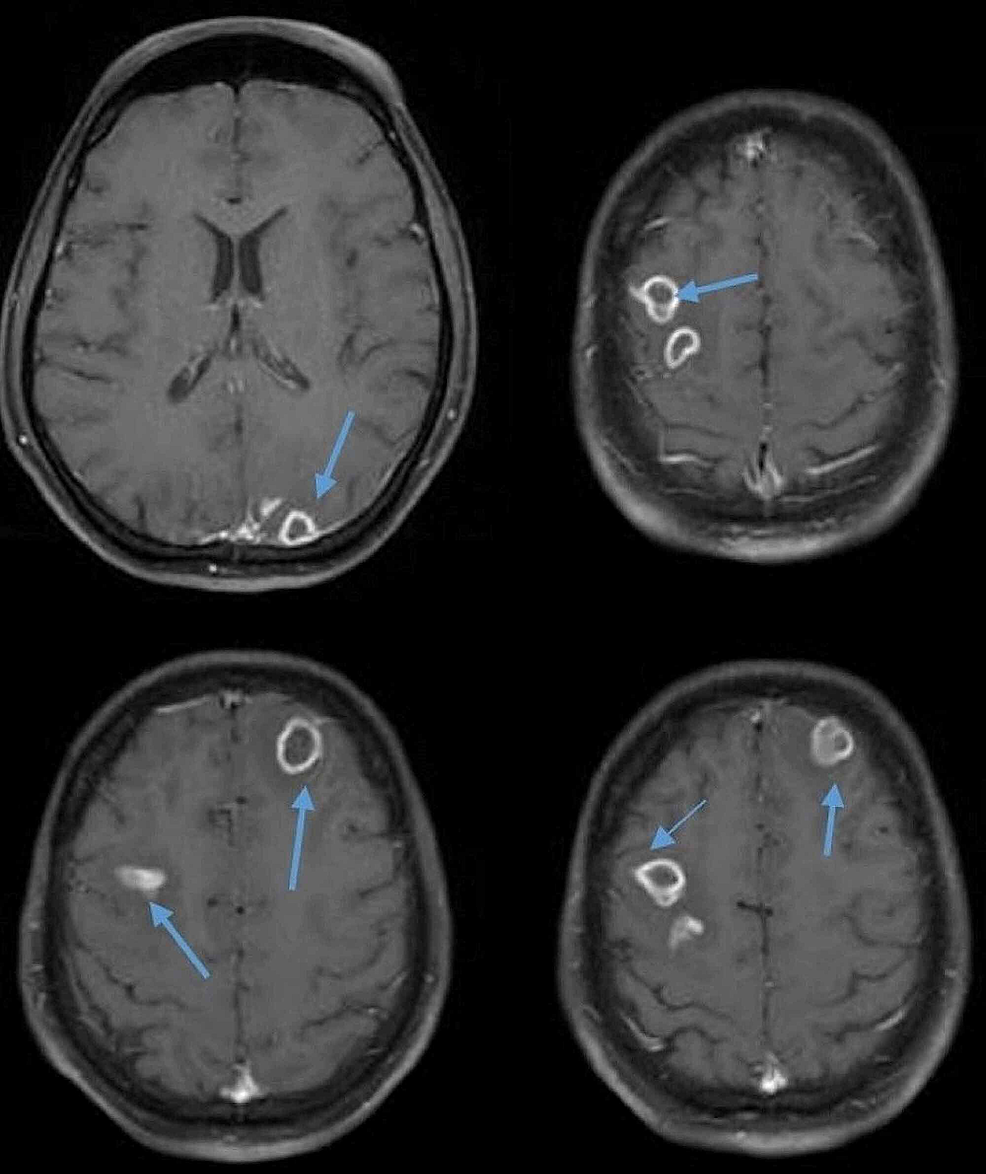

A brain abscess occurs when bacteria or other pathogens infect the brain, forming a pocket of pus. In children, these infections often start as routine sinusitis or ear infections that travel to the brain. Though rare, brain abscesses are considered medical emergencies because they can rapidly worsen if untreated. Early recognition and treatment are critical to preventing complications and promoting full recovery.

Brain abscesses usually occur when an infection in another part of the body, such as the sinuses or ears, spreads to the brain. The immune system often contains infections in children, but under certain conditions, bacteria can travel through the bloodstream or directly invade brain tissue. Children recovering from severe viral infections are at higher risk, as viral illness can weaken local defenses and make the brain more vulnerable to secondary bacterial invasion. https://my.clevelandclinic.org/health/diseases/21777-brain-abscess

Recognizing early brain abscess symptoms in children is crucial. Common warning signs include persistent headache, swelling around the eyes, fever, nausea, and neurological symptoms such as seizures or weakness. Parents should seek prompt medical attention if a child exhibits these symptoms, especially following a recent sinus or ear infection. Pediatric specialists emphasize that timely diagnosis can significantly improve outcomes.